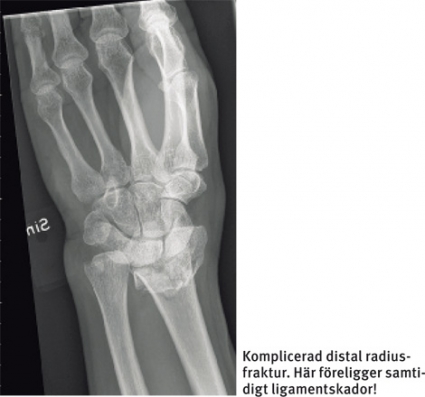

Av TFCC-skadorna sker över 90 procent i samband med distal radiusfraktur. En axial förkortning större än 3 mm och en dorsal felvinkling överstigande 25° är starkt associerad med TFCC-skada [1]. Vid samtidig fraktur i ulnastyloidens bas bör man också räkna med total instabilitet i distala radioulnarleden eftersom även det djupa TFCC-fästet sannolikt rupturerat. Frakturer distalt i ulnastyloiden ger i sig inte upphov till någon instabilitet. Man ska ha i åtanke att TFCC-skador naturligtvis också förekommer utan samtidig fraktur eller andra röntgenologiska förändringar.

Vid kraftigt dislocerade intraartikulära distala radiusfrakturer bör man utgå från att det alltid finns associerade ligamentskador. Dessa behöver inte alltid specifikt opereras, men de ska alltid värderas, inte minst eftersom de kan påverka efterbehandling och rehabilitering.

Ligamentskador i handleden är mycket vanliga. Vid distala radiusfrakturer förekommer samtidigt ligamentskador i minst 50–75 procent av fallen, förvisso oftast partiella [1], där skador i triangulära fibrokartilaginära komplexet (TFCC) dominerar. Nya rön visar att ligamentskador är vanliga också vid scaphoideum-fraktur [2]. I cirka en tredjedel av fallen av midjefraktur på scaphoideum fann man samtidig skada på skafolunära ligamentet. 20 procent av dessa var totala rupturer.